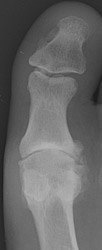

Osteoarthritis: Lateral View - Large dorsal osteophytes at 1st MTP jointOsteoarthritis: AP View - Large osteophytes and joint space narrowing at 1st MTP jointOSTEOARTHRITIS non-inflammatory deterioration of articular cartilage with articular surface and marginal bone formation.

Radiographic manifestations may include marginal osteophyte and subchondral bony cyst formation, eburnation, and interosseous joint space narrowing. First metatarsal phalangeal joint osteoarthritis is frequently associated with hallux valgus deformities. Calcaneal spurs, when manifested, are sharp and well defined.